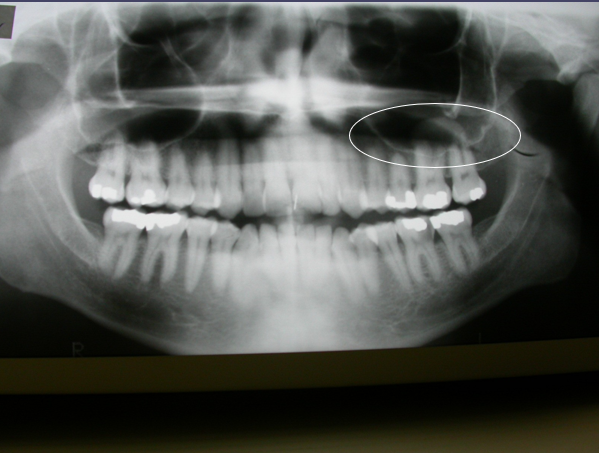

What is this radiographic finding?

Aneurysmal Bone Cyst

you can see that there is kind of a

multilocular radiolucency in this particular area

Antral Pseudocyst